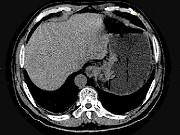

问题 男,75岁,吞咽有梗阻感,消瘦、乏力、中上腹痛,影像检查如图,最可能的诊断是()

选项 A.食道癌 B.胃窦癌 C.贲门癌 D.慢性胃炎 E.胃淋巴瘤

答案 C